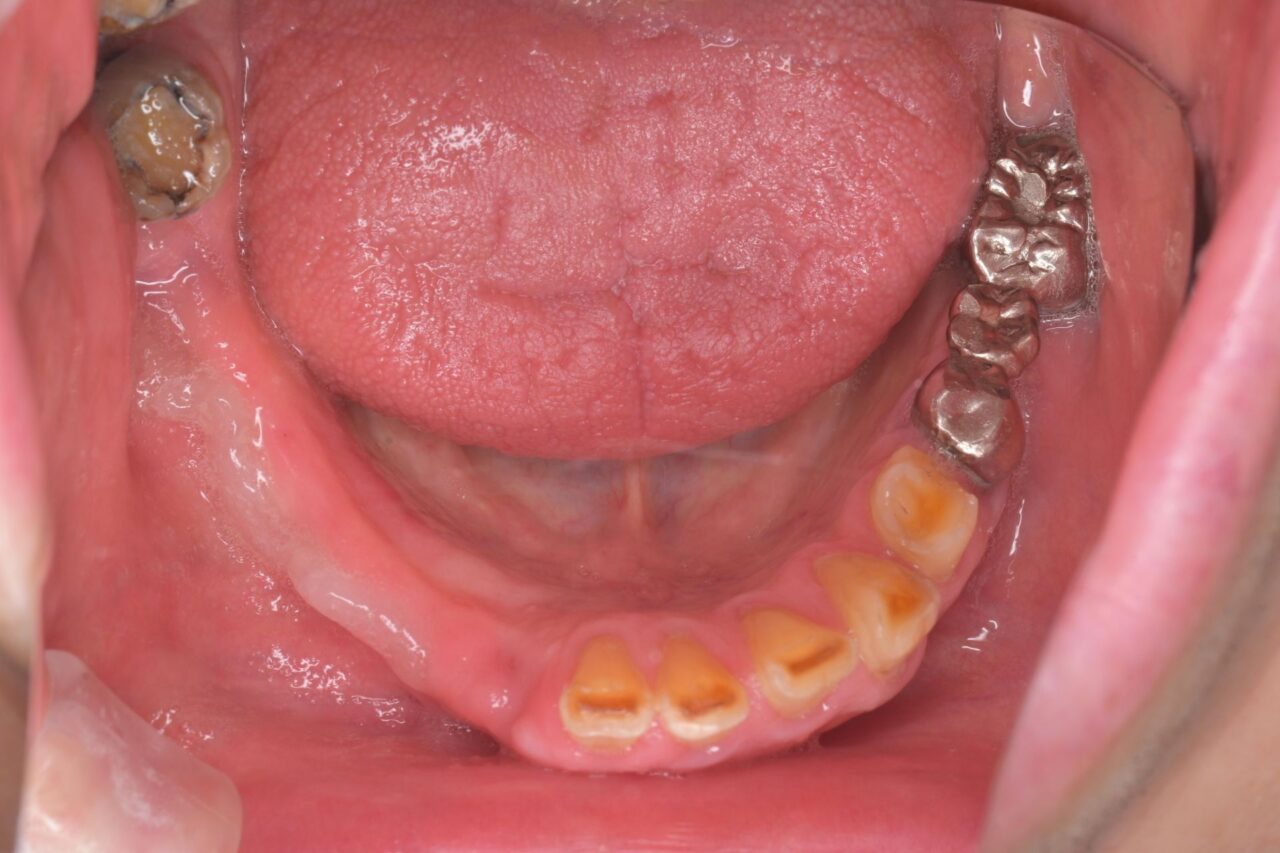

下面

親知らずが残っていますね。

びわ湖大津デンタルクリニックでは、不要な親知らずは即抜歯です。

ブリッジも不衛生かつ虫歯になっていますので、迷わず撤去。